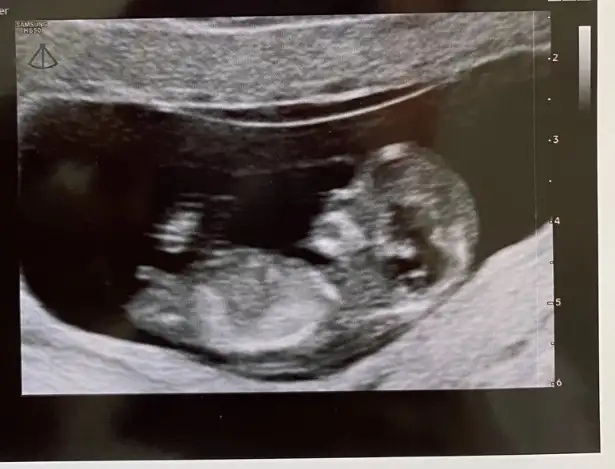

Kız gibi geldi banaBakar mısınız lütfen

Doktor da öyle demiş ama keson değil benziyor demiş bakalım ne olacakKız gibi geldi bana

Bazilari erkek diyo bazilari kiz ama 2 doktorda kiza benzetti bidaki ayin 18de gircem ozamn net soyleriz dedile rpekde emin olmadilarerkek gibi geldi bana